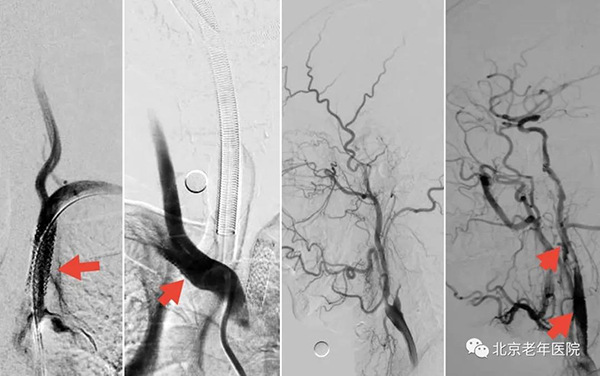

术中造影发现:左侧颈内动脉闭塞,远端供血分支代偿不足;双侧锁骨下动脉重度狭窄。同期全麻下行左侧颈内动脉血栓性闭塞开通术+双侧锁骨下动脉支架置入术(红箭头),术后患者情况稳定,病情明显好转。患者从入院时右侧肢体活动不能,言语不利到出院时能正常交流、正常持物与独立行走。